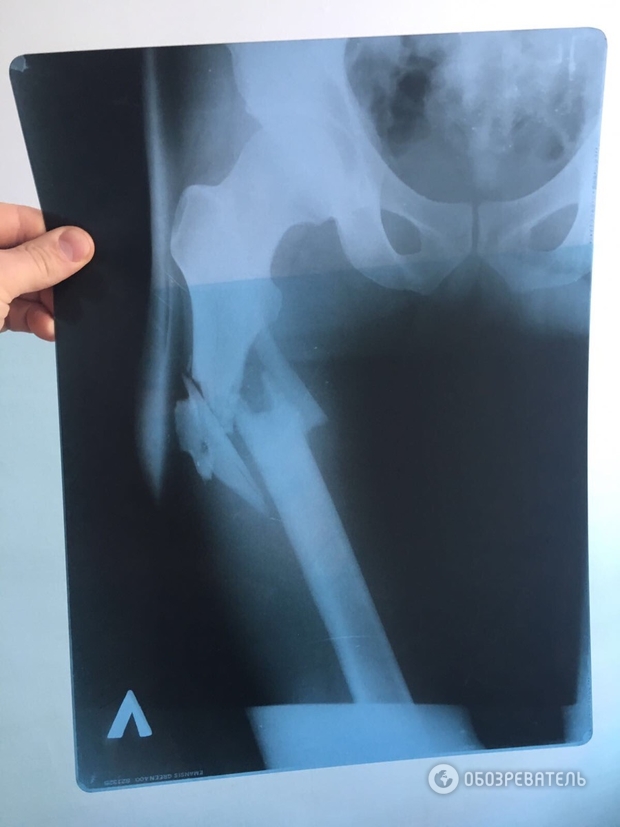

Изданию также удалось заполучить рентгеновский снимок простреленной ноги Химикуса. Учитывая положение входного и выходного отверстий от пули, можно предположить, что пуля «шла» сверху вниз.

По информации источника «Обозревателя», данный факт (смещение костей) подтверждает, что Пашинский выстрелил сверху в ногу Вячеславу Химикусу, а не из положения лежа, как нардеп утверждал ранее.